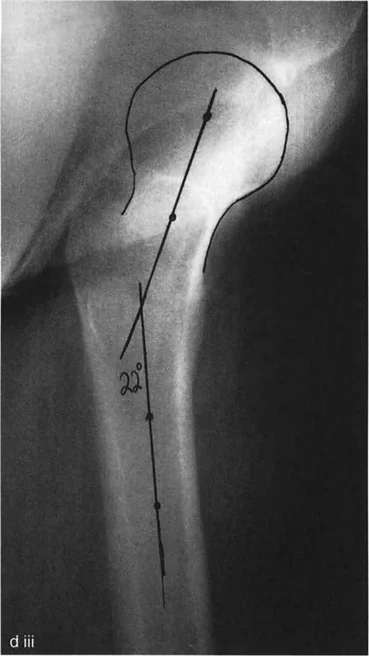

يمكن استخدام الطرق الرياضية لتحديد دوران عنق الفخذ ومحور الساق والشظية باستخدام صورتين إشعاعيتين متعامدتين (أمامية خلفية وجانبية). يُعرف هذا بتحليل المستوى المائل.

يمكن تحويل الزاوية المقاسة بين عنق الفخذ وجسم الفخذ في الأشعة السينية الأمامية الخلفية والجانبية مثلثيًا لتحديد الدوران الأمامي الحقيقي. وبالمثل، يمكن حساب المستوى الذي يحتوي على أطراف الكاحلين الإنسي والوحشي بالنسبة للمستوى الأمامي للركبة.

تقنية حاسمة: من الضروري للغاية الحصول على كل من الأشعة السينية الأمامية الخلفية والجانبية للكاحل والورك متعامدة مع وضعية الرضفة للأمام. إذا تم تدوير الركبة أثناء التصوير بالأشعة السينية، فستكون الحسابات غير صالحة تمامًا.

شكل يوضح كيفية قياس دوران عنق الفخذ باستخدام الأشعة السينية، وهو أمر حيوي لتحديد التشوه في الفخذ.